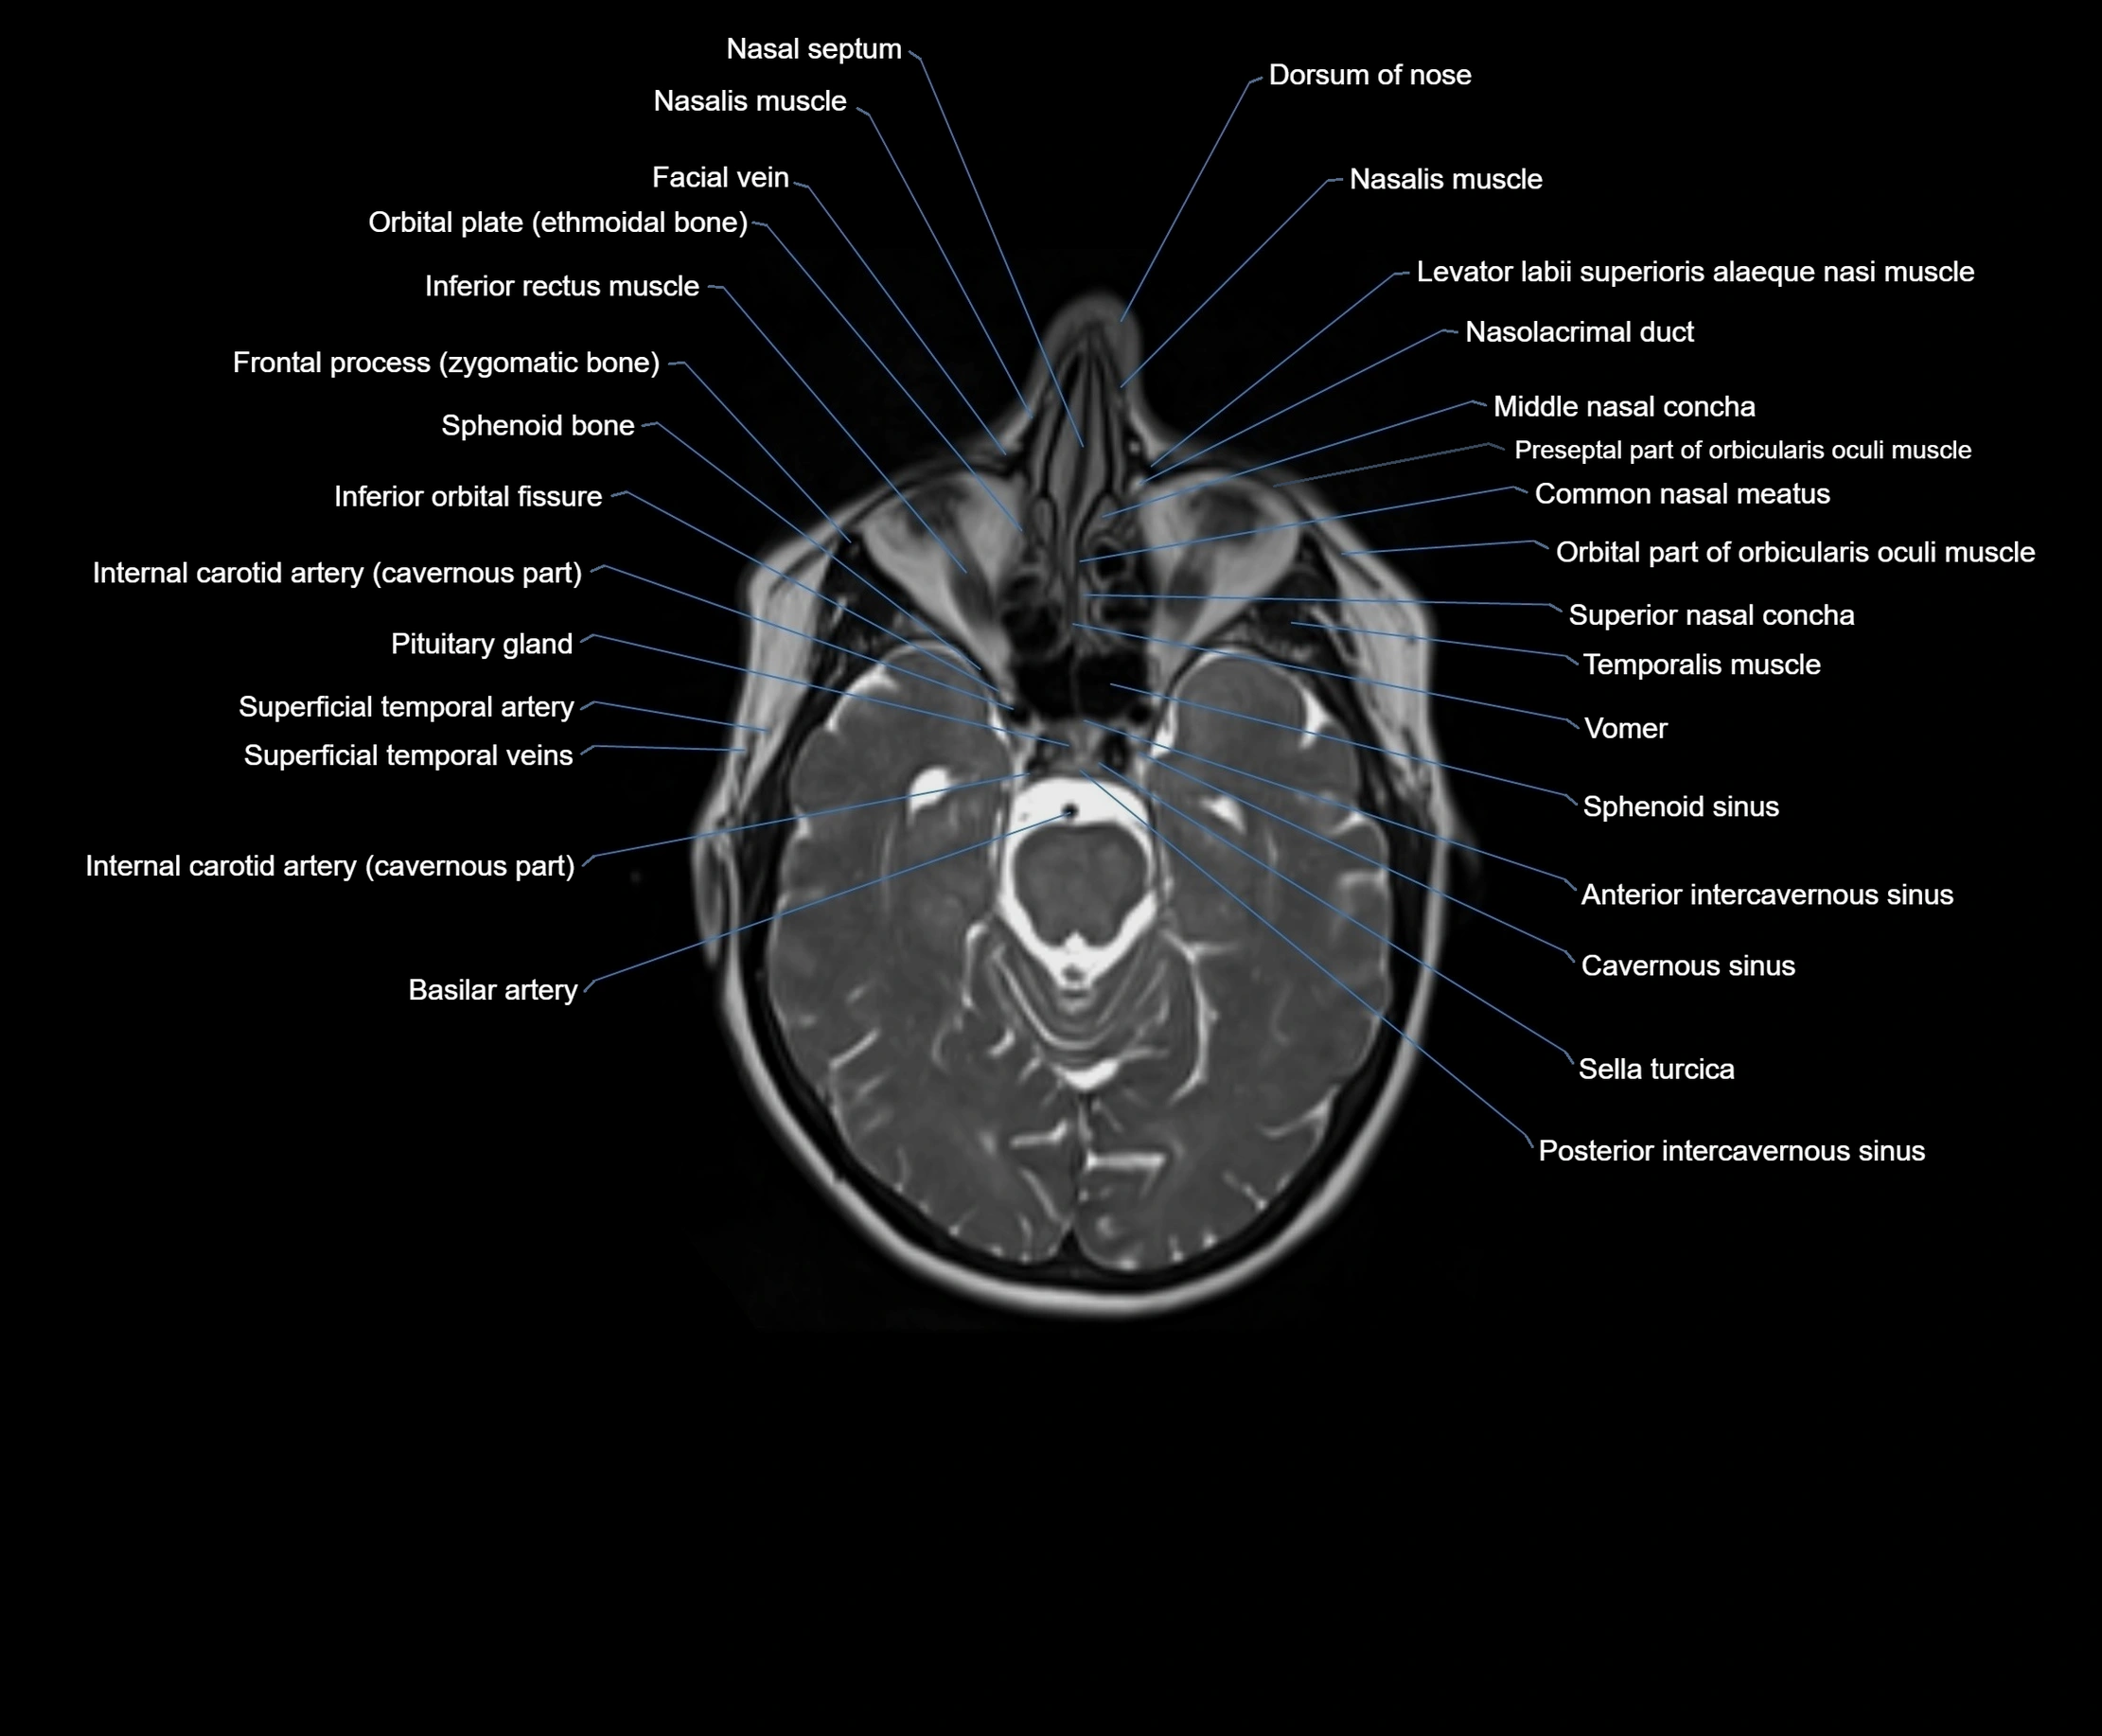

MRI images